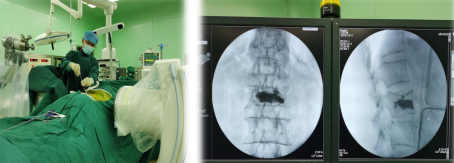

脊柱科手术团队采用骨科机器人为67岁患者进行腰椎疏松性压缩性骨折微创手术

此次机器人手术中,先由C型臂对患者进行三维影像扫描,图像被同步传输至手术机器人系统。医生在导航系统屏幕上设计好钉道,沿机器人导向器,钻入导针,插入工作套管。C臂透视侧位钻头前端位于椎体前1/3,插入球囊扩张器,注入骨水泥,透视可见椎体高度恢复满意,骨水泥分布良好。手术非常成功。